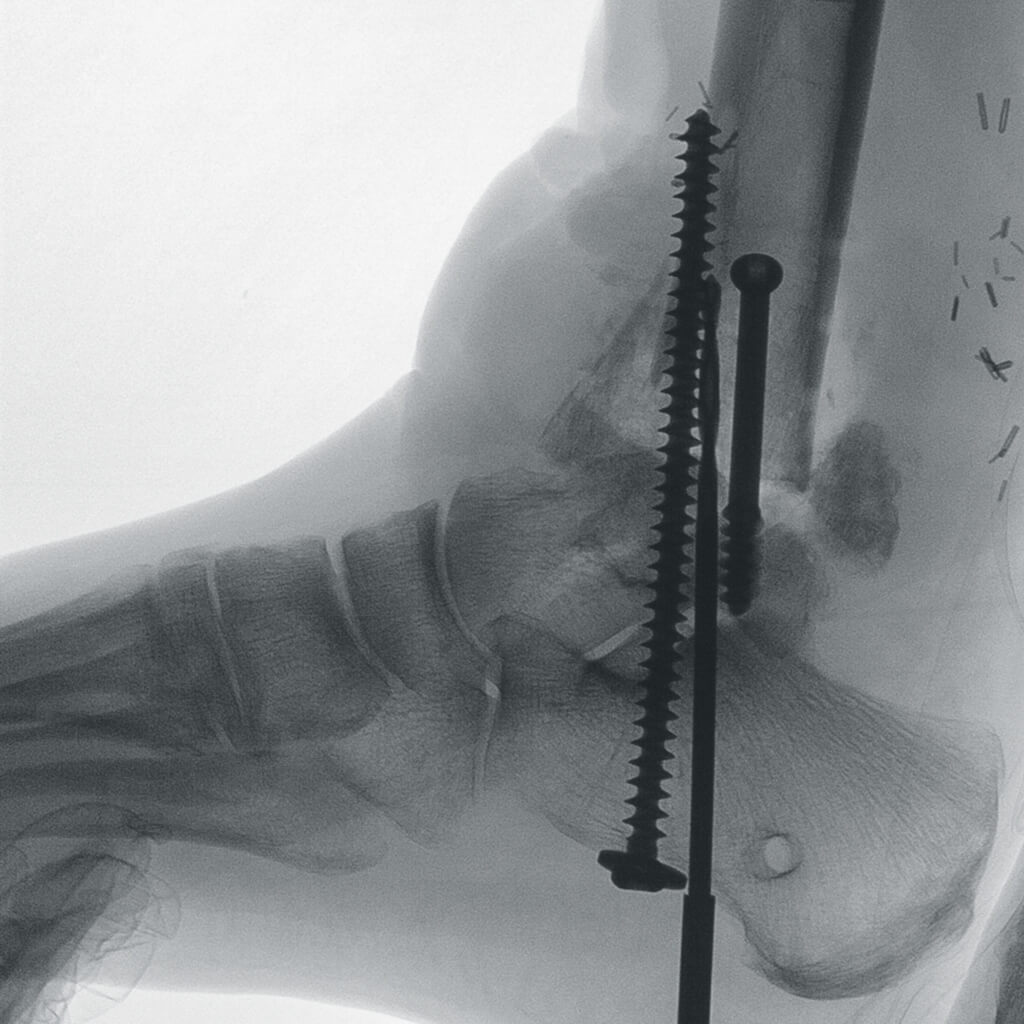

Полное отсутствие искажений снимков в сочетании с высоким динамическим диапазоном широко востребованы как при сложных операциях в нейрохирургии, сосудистой хирургии, инвазивной радиологии, так и в гибридных областях применения, а также в ортопедии, травматологии. В сосудистой хирургии особенно важны высокий динамический диапазон и пространственное разрешение, обеспечивающие детальную визуализацию даже мельчайших сосудов. Специализированное программное обеспечение SmartVascular позволяет проводить настройку системы для васкулярных операций и сосудистой хирургии.

Точная визуализация анатомических деталей, мягких тканей и костных структур обеспечивается за счет светочувствительной матрицы 3kх3k пикселей с высоким динамическим диапазоном.

Автораспознавание металла

Винты, пластины, импланты и хирургические инструменты автоматически распознаются при попадании в видимое поле аппарата. В этом случае происходит корректировка мощности дозы облучения для улучшения качества снимка.